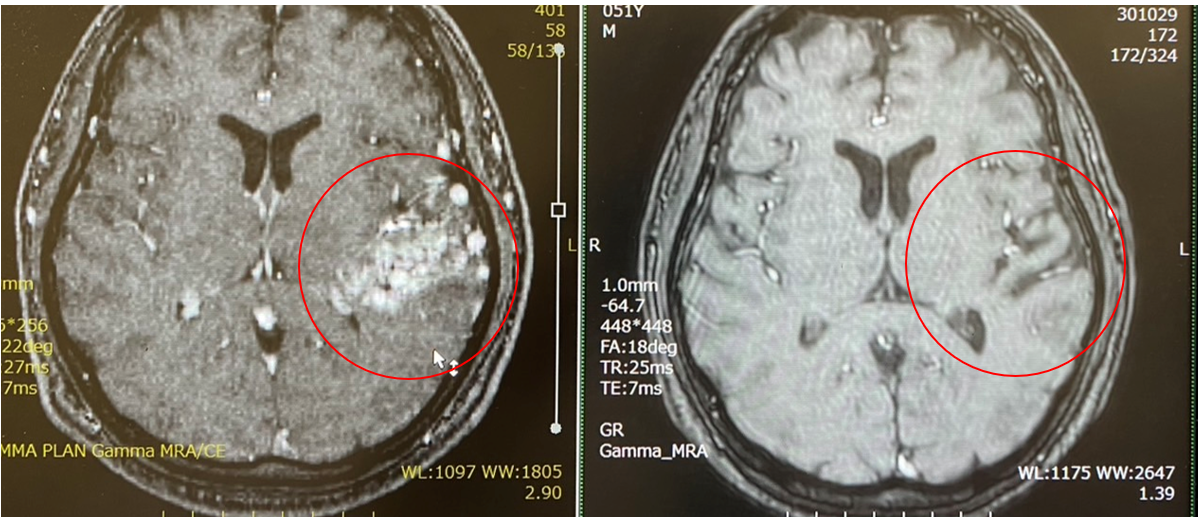

AVM(脳動静脈奇形)ガンマナイフにて完治!

茨城在住のAVM患者さん(左図)。いまから10年前に初めていらっしゃり、2度のガンマナイフにて今回外来にて完全消失を確認。しかも放射線障害もなく文字通り完治となった。その時に外来で印象的だったのは「林先生にすべてをかけた!もし治らなくとも、途中出血したとしても、この先生にすべてをかけた。だから途中何があっても不安にはならなかった。それは最初の外来のときに林先生に決めようと思ったときからであった、、」とお言葉を頂いたことでした。同じ患者経験を持つものとして、とても客観的に共感を持てる言葉でした。今後も「治します!」「ベストを尽くします!!」と言い切れる医者になれるように。そして、患者さんにも「こういう人生にしたい!」「これがしたい!!」ということをフランクに言っていただける存在になれるよう精進したいと考えています。そして、最後に息子さん(現在12歳、当時2歳)から「本当に感謝しています!」と言って頂けました!!